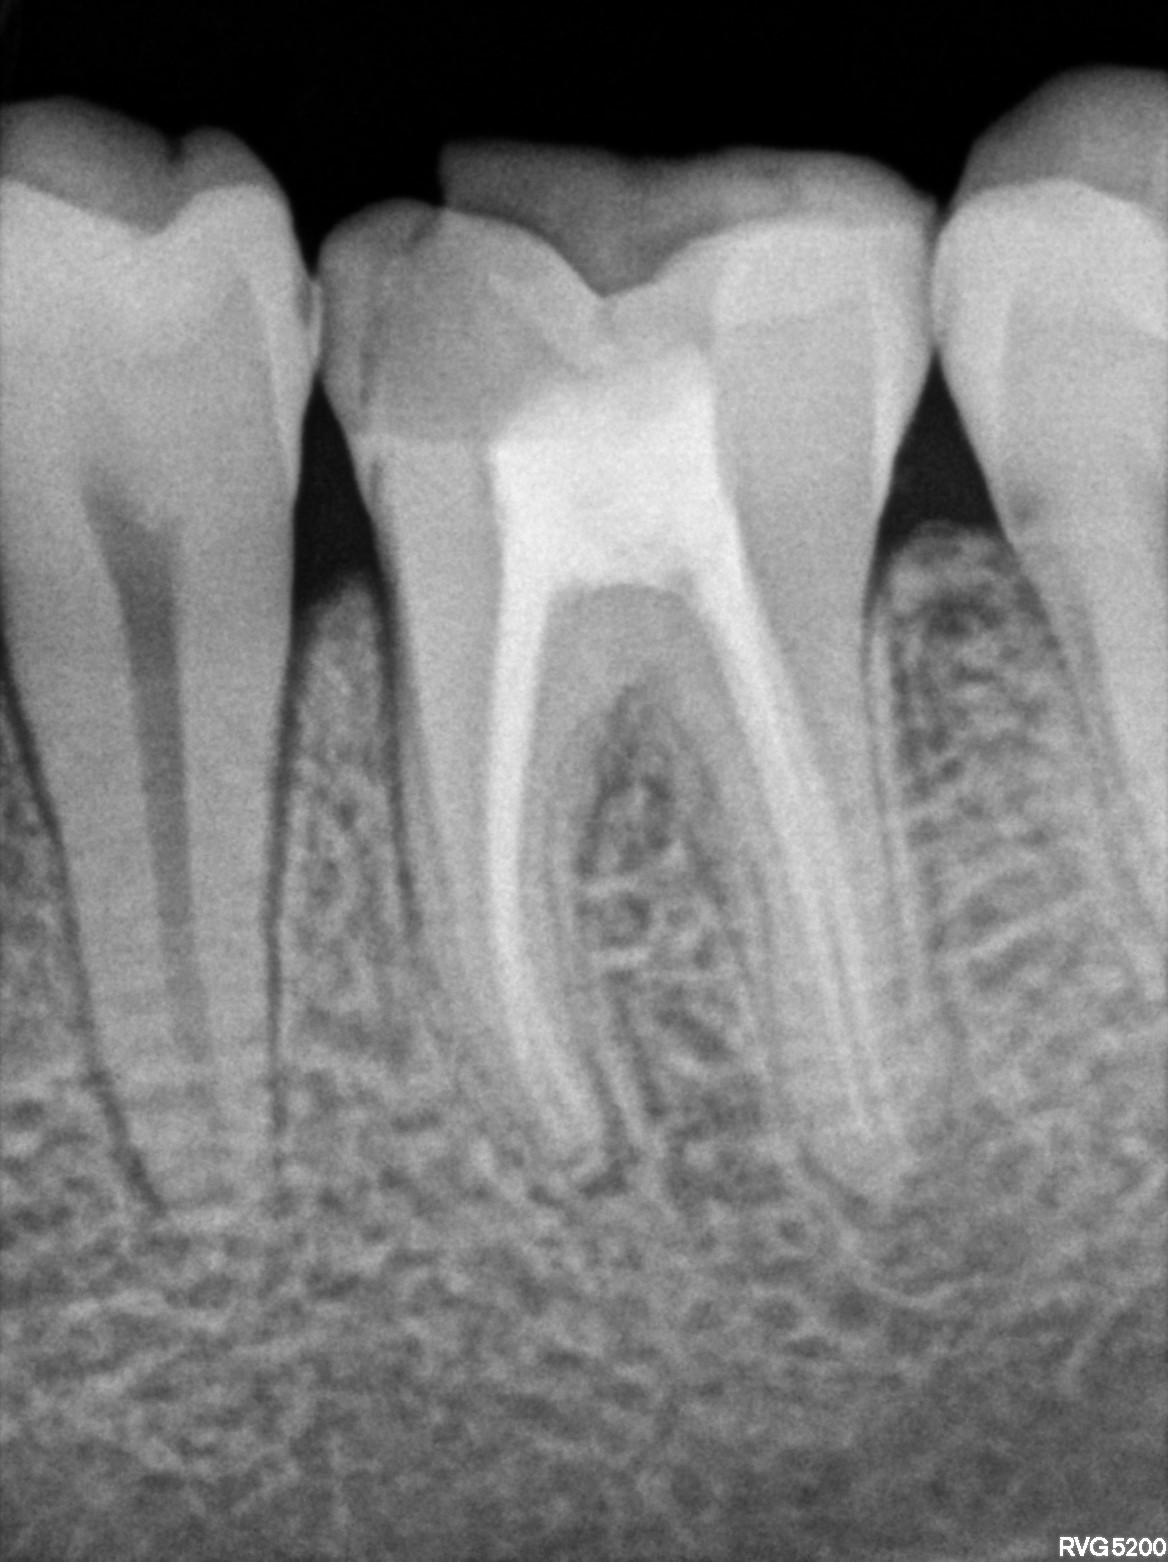

Dental Radiographs FHIR: DocumentReference · LOINC 24641-7

36.jpg

24641-7

46.jpg